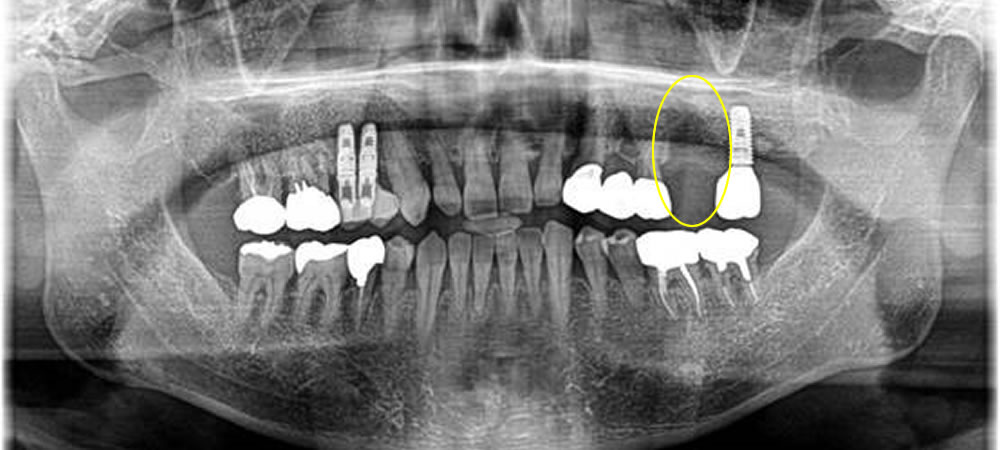

歯周病で歯を失った部分をインプラントで治療した症例

年齢

60代

性別

男性

症例を見る